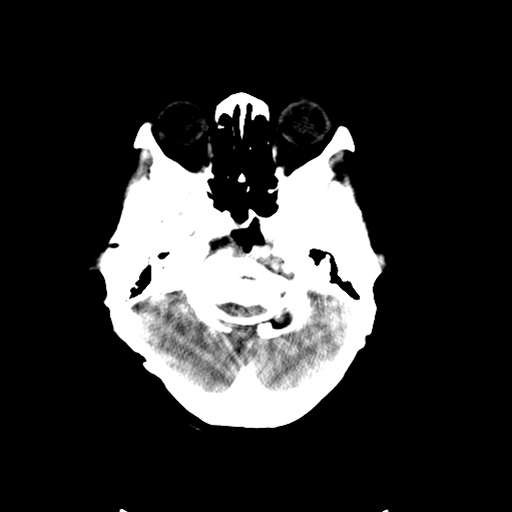

标题: CL0976:颅骨凹陷征 [打印本页]

标题: CL0976:颅骨凹陷征

女,56岁,头痛,没有其他的神经系统的阳性体征

颅底陷入是枕大孔周围骨,包括枕骨基底部、髁部和鳞部上升向颅腔内陷入的畸形。环、枢椎也随之上升、突入。多属枕骨及环枢椎先天性发育异常,也可继发于引起颅底软化的疾病、成骨不全或佝偻病等。

颅底凹陷是压迫小脑所以应该有受压的症状,如走路不稳,醉酒状态等.

颅底凹陷.典型.